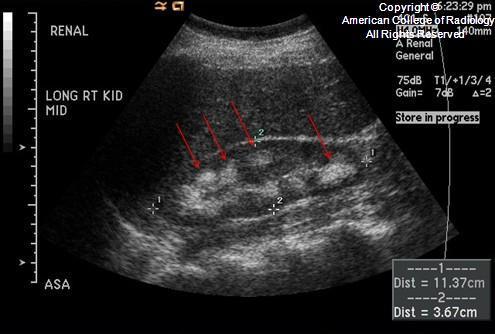

Medullary nephrocalcinosis is more common than

cortical nephrocalcinosis

DDX for medullary nephrocalcinosis